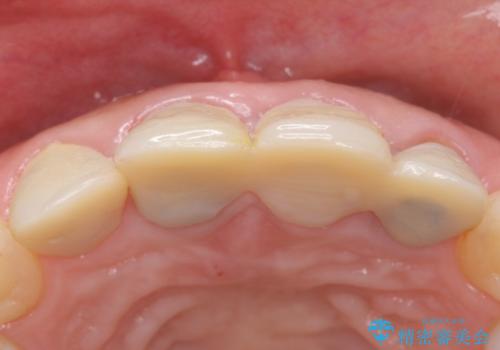

- 前歯を綺麗にしたいとのことで来院されました。

色調・適合ともに改善するために一度被せ物を外し、歯の形を整えた後に新しい被せ物を装着していきます。

- 右上12左上12/仮歯4本+ジルコニアクラウン4本:44,000+484,000円 左上2/根管治療(保険)費用は治療当時の料金となります